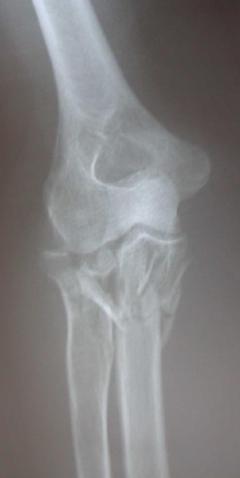

Περίπτωση 2ου ασθενούς

Προεγχειρητική